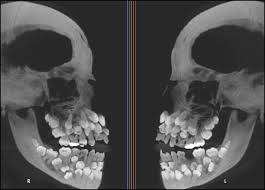

In popular culture, the search term dustin multiple hyperdontia often refers to the actor Gaten Matarazzo, who plays Dustin Henderson in the series Stranger Things. Matarazzo has Cleidocranial Dysplasia and has been open about his experience with Multiple hyperdontia, helping to raise awareness about the condition. In CCD, patients may have multiple hyperdontia images revealing a jaw full of unerupted teeth, often described as having extra teeth growing in gums that block normal eruption.

Visible signs of Multiple hyperdontia include the eruption of extra teeth into the oral cavity, overcrowding, or the displacement of permanent teeth. In some severe presentations, patients may describe having hyperdontia multiple rows of teeth, resembling a shark’s dentition where a second row of teeth appears behind the primary arch. Another tell-tale sign is the failure of a permanent tooth to erupt on schedule; often, an extra tooth is blocking its path. In some instances, retained primary teeth that fail to fall out at the expected age can indicate the presence of an underlying supernumerary blocking the permanent successor.

X-rays are essential for confirming Multiple hyperdontia. A standard Panoramic radiograph (OPG) provides a broad view of the jaws and is usually the first step in identifying supernumerary teeth. However, 2D images have limitations; they show the presence of teeth but not their exact depth or relationship to other structures.

For more complex cases of Multiple hyperdontia, Cone Beam Computed Tomography (CBCT) is the gold standard. CBCT provides a 3-D view, allowing the surgeon to see the exact position of the extra teeth growing in gums relative to nerves, roots of adjacent teeth, and the sinus floor. This is crucial for planning the extraction of teeth growing in gums that cannot erupt naturally, minimizing the risk of damage to vital structures during surgery.

It is important to distinguish Multiple hyperdontia from hypodontia. While Multiple hyperdontia refers to an excess of teeth, hypodontia is the congenital absence of teeth. Interestingly, both conditions can sometimes appear in the same patient or within the same family, suggesting a complex genetic interplay regulating tooth number. This phenomenon is known as “concomitant hypohyperdontia”. Additionally, patients researching their symptoms might look for multiple hyperdontia images to compare with their own condition, often confusing extra teeth with retained baby teeth that have not yet fallen out. A professional diagnosis utilizing radiographic imaging is the only way to confirm Multiple hyperdontia.